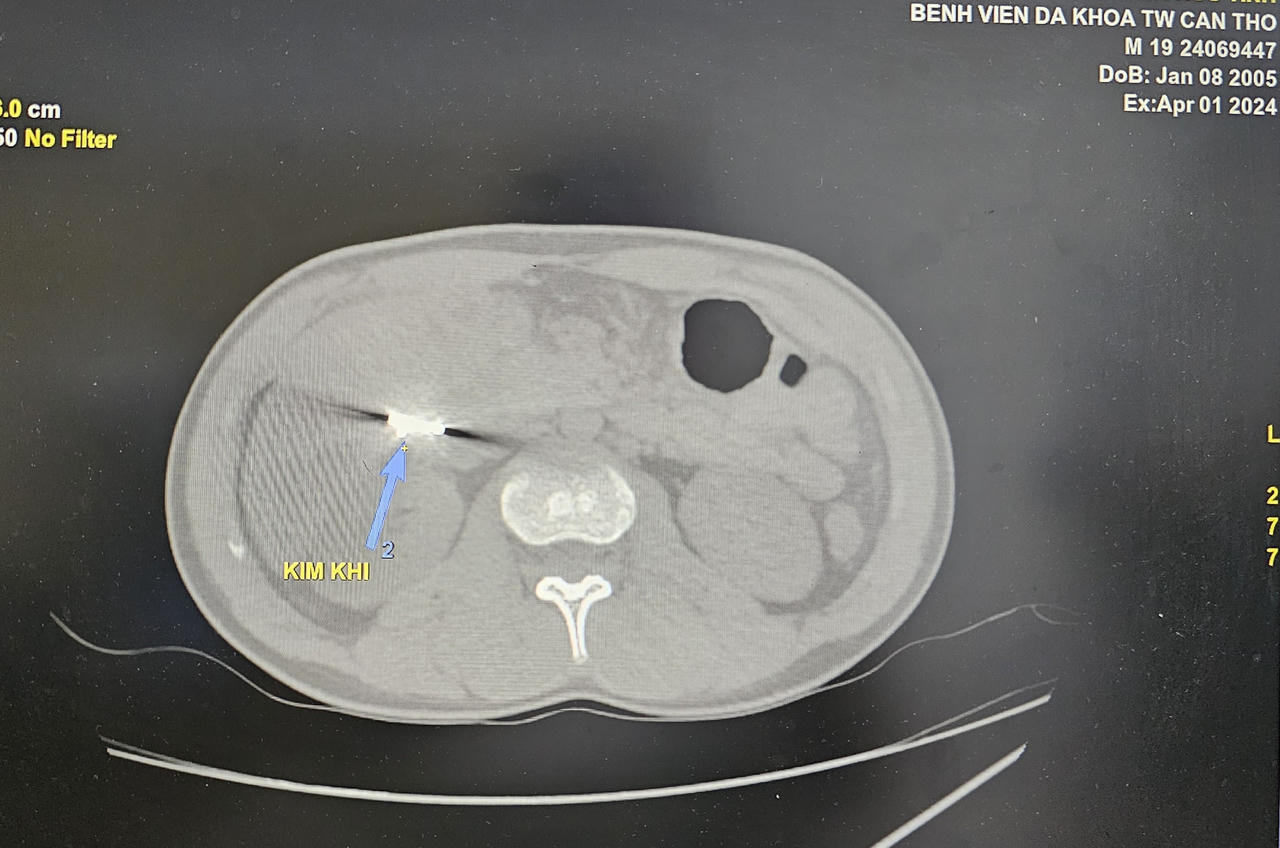

Hình kim khí trên phim chụp cắt lớp vi tính bụng có cản quang |

Các bác sĩ tiến hành thăm khám và thực hiện các xét nghiệm. Kết quả chụp cắt lớp vi tính bụng có cản quang ghi nhận dị vật cản quang kim loại dưới gan phải kích thước khoảng 2x1cm, áp xe vùng hạ sườn phải. Bệnh nhân có chỉ định phẫu thuật nội soi lấy dị vật. Sau phẫu thuật, bệnh nhân ổn định, vết mổ khô.